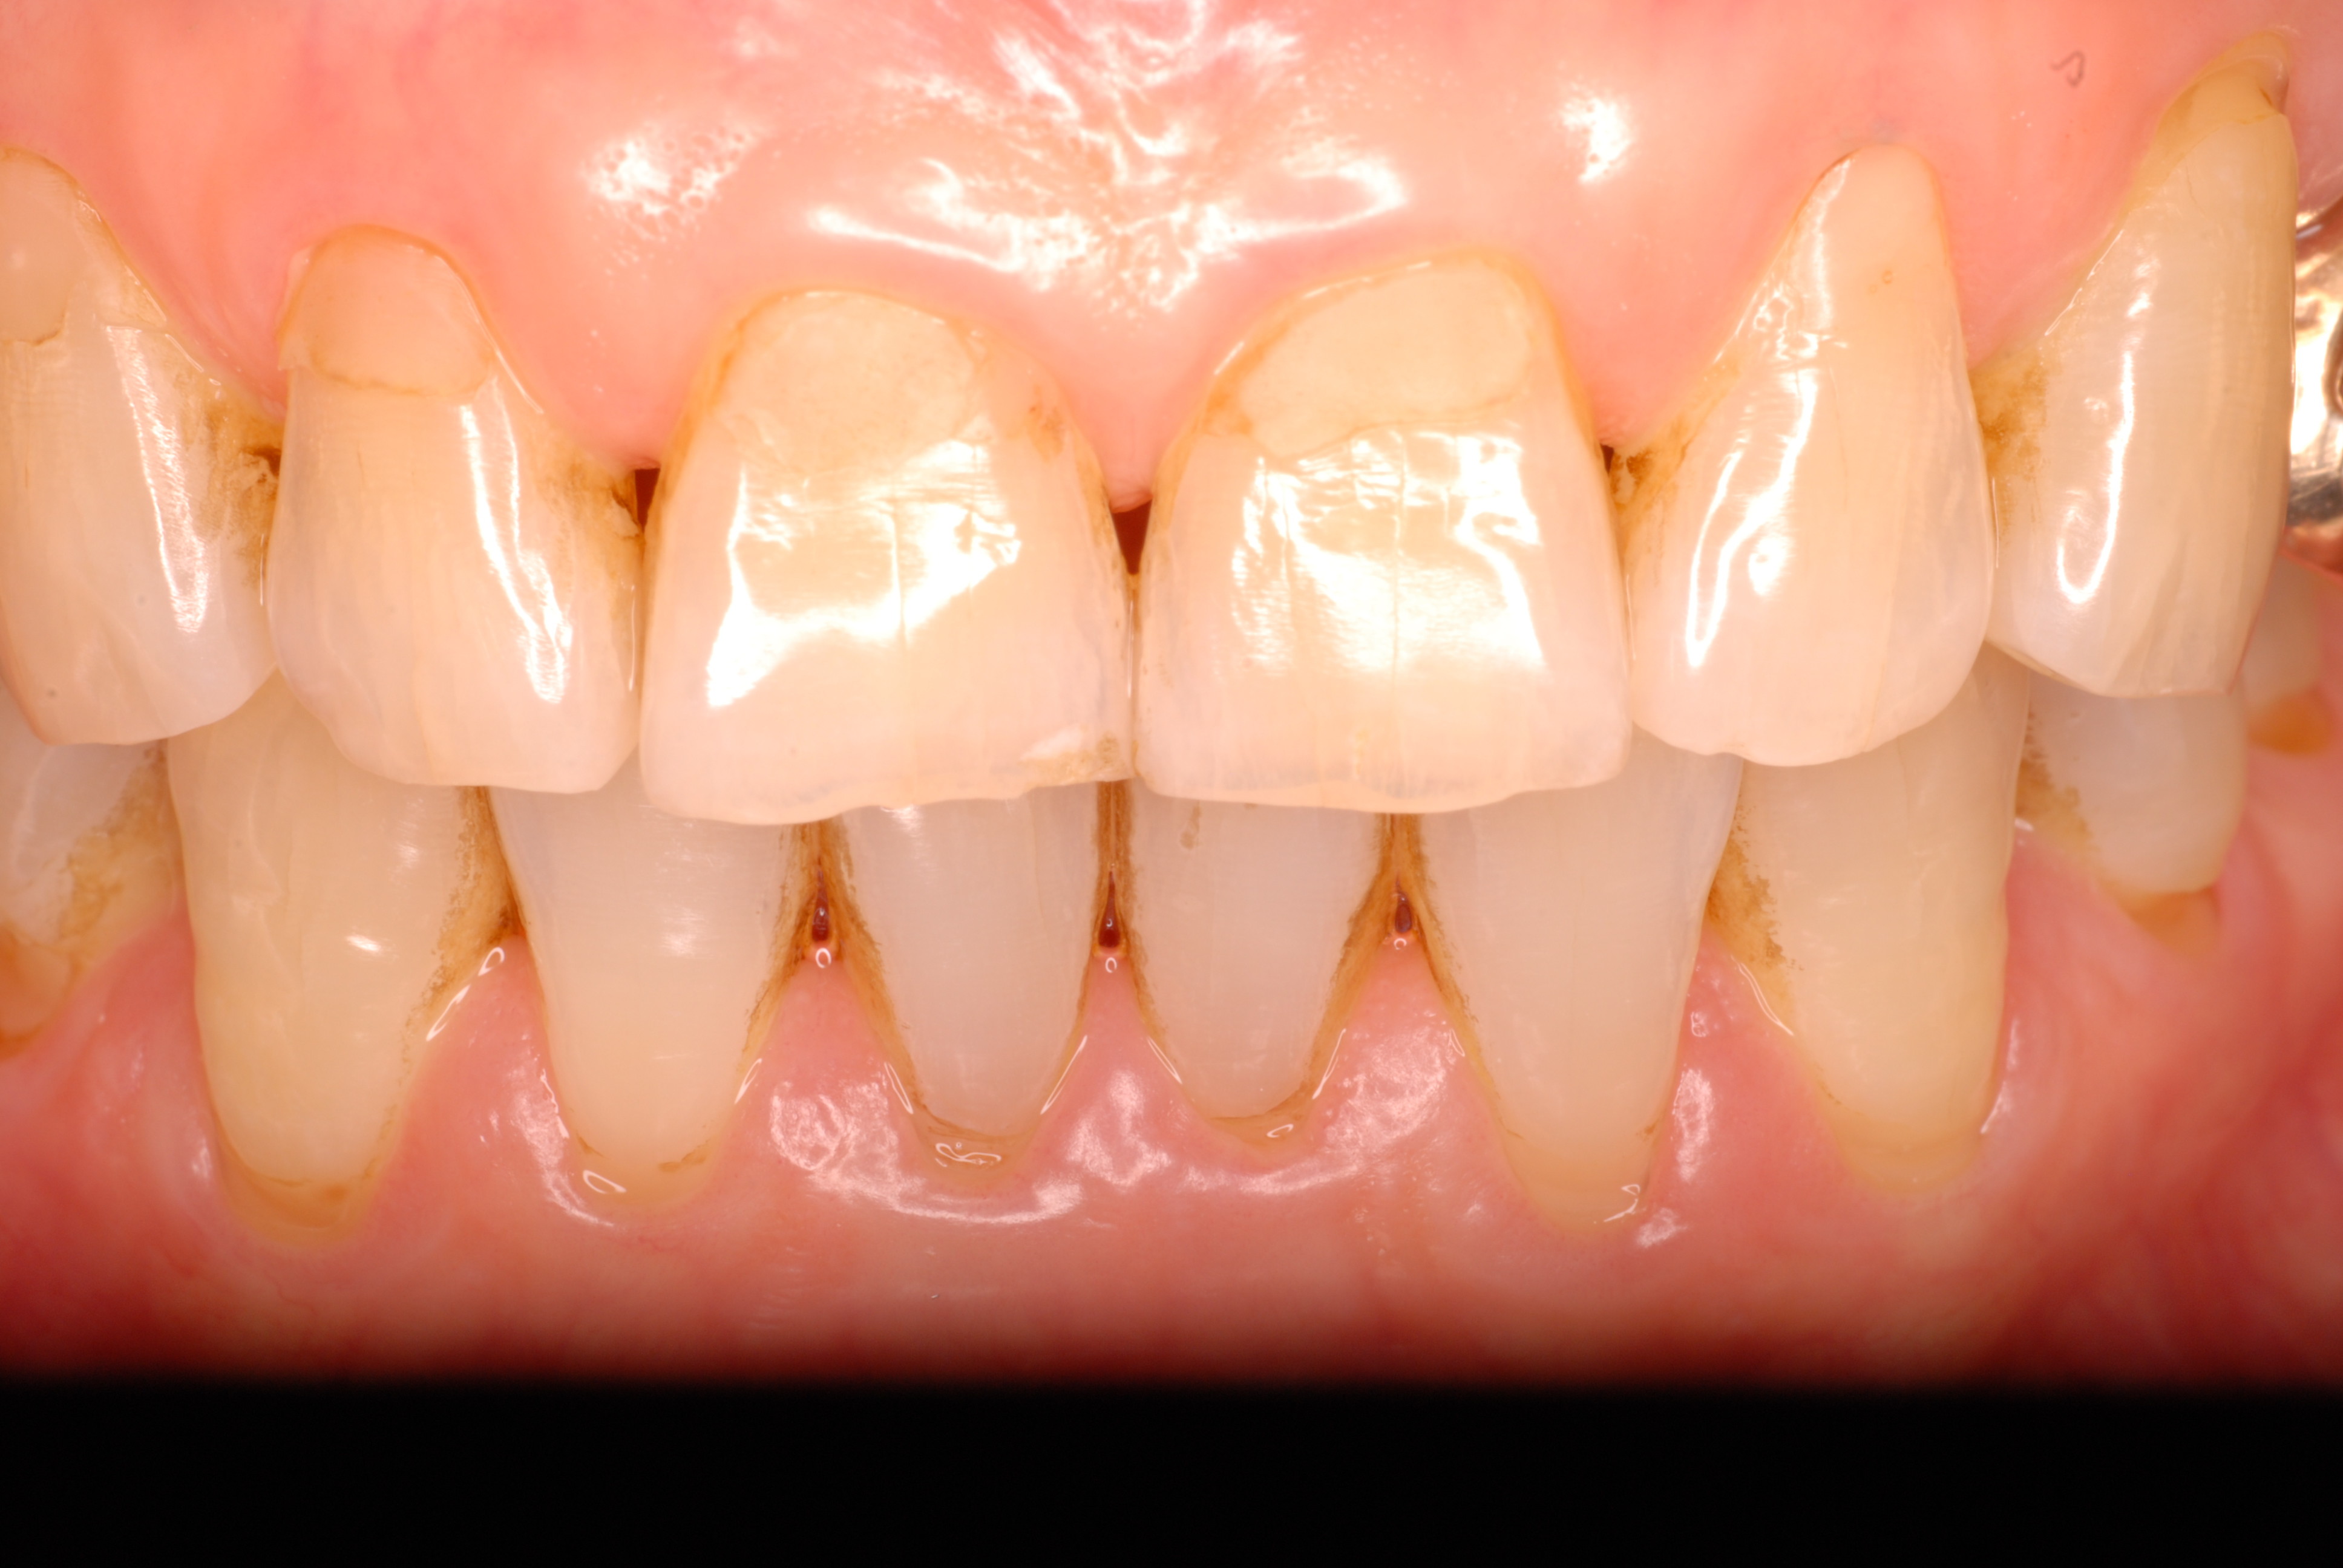

少しうまくなり綺麗な歯肉の状態になりました。

数年経過した上の歯です。折れた歯は差し歯になっています。その隣の

白い歯が差し歯にしていない歯です。神経はありません。